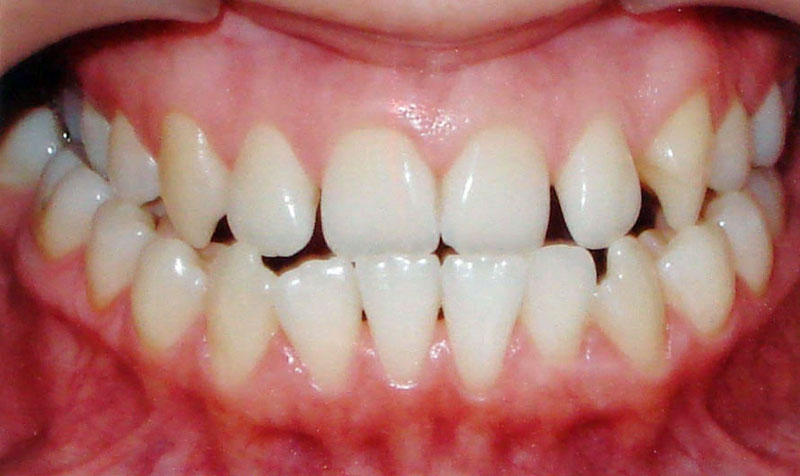

Начну с самого простого. Мальчик, 6 лет. Носил съемную плстинку 4 мес. В таком возрасте брекеты еще, как правило, не используют.

А это уже молодой человек 10 лет. Тоже получилось справиться без удаления. Хоть оно и было показано. Но мальчик очень упорно носил специальные аппаратики и резиночки. Покажу со всех сторон. Этот случай победил в конкурсе на конференции